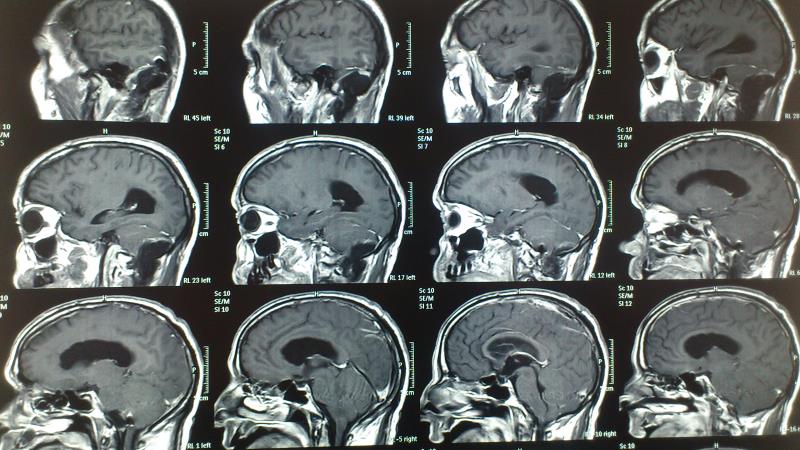

Ασθενής  άνδρας 55 ετών  προσήλθε λόγω αστάθειας βάδισης  και πάρεσης  των κατώτερων εγκεφαλικών συζυγιών  ( ΙΧ,Χ,ΧΙ ). Ο  έλεγχος με μαγνητική τομογραφία εγκεφάλου ανέδειξε εικόνα συμβατή  με μηνιγγίωμα ινιακού τρήματος με σημαντική πίεση επί του στελέχους. Ο ασθενής υποβλήθηκε σε αριστερή  Far Lateral Transcondylar προσπέλαση. Μετεγχειρητικά ο ασθενής παρουσίασε ήπια επιδείνωση της πάρεσης των κατώτερων εγκεφαλικών συζυγιών που ωστόσο αποκαταστάθηκε σταδιακά στα προεγχειρητικά επίπεδα Ο μετεγχειρητικός απεικονιστικός έλεγχος ανέδειξε ολική αφαίρεση του όγκου.

Προεγχειρητικός απεικονιστικός έλεγχος